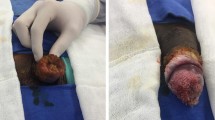

A 38-year-old African American female with no significant past medical history presented to the emergency department as a referral for evaluation in May 2020 owing to a large bladder mass found incidentally on imaging at an outside hospital. At the time of presentation, her only symptoms were recurrent urinary tract infections, of which she reported 4–5 occurrences in the last year, intermittent spotting on toilet paper, and occasional stress urinary incontinence. We repeated a computed tomography (CT) of the abdomen and pelvis at our institution and identified the mass occupying much of the posterior bladder wall with suspicious but indeterminate invasion of the uterus and cervix. Additionally, bilateral hydroureteronephrosis was found with the left ureter more dilated than the right. Subsequently, the patient underwent cystoscopy with bilateral stent placement and a biopsy sample was taken of the bladder lesion as well as a lesion of the left labia. Pathology results returned for both showing findings consistent with condyloma acuminatum as well as low-grade squamous intraepithelial lesion of the cervix. The patient then proceeded with a transurethral resection (TUR) of the mass. A second TUR with excision of the left labial mass was planned owing to the remaining tumor burden and concern that there may be an underlying malignancy. This attempt, however, was aborted owing to diffuse transformation now involving the urethra. After careful consideration and discussion, it was determined that bladder salvage was not feasible, and the best course of action would be bladder removal. She then underwent a radical cystectomy with the creation of a neobladder and self-catheterizable stoma and a hysterectomy in early September 2020, with biopsy samples taken intraoperatively. Final pathology results returned showing atypical condyloma proliferation of the urinary bladder wall and squamous cell carcinoma of the urinary bladder, urethra, and anterior vagina. Staging of the malignancy was determined to be IIIA (pT4a, pN0, cM0) and grade 1 owing to microscopic residual tumor margins of the urethra, as the condyloma was found to extend beyond the urethral meatus. Considering the staging reflected positive margins, adjuvant chemotherapy was carefully considered. She then began chemo and radiation in November 2020 and completed it in February 2021. Today, she is managed with close monitoring by surveillance imaging with urology and medical and radiation oncology with no recurrence of disease demonstrated on imaging.

Written informed consent was obtained from the patient for publication of this case report and any accompanying images. A copy of informed consent is available for review by the Editor-in-Chief of this journal.